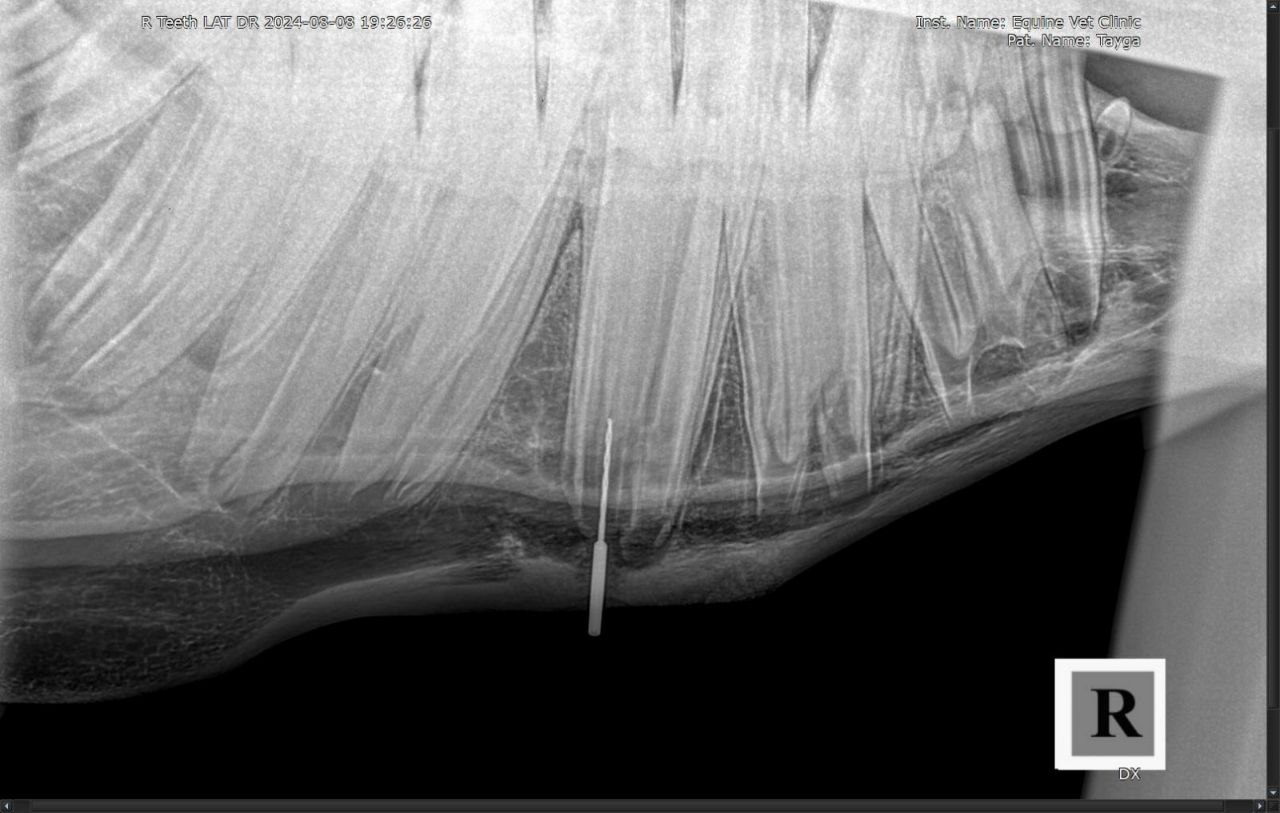

Результаты рентгенологического исследования: наблюдается неравномерная рентгенологическая плотность вокруг верхушки корня и утолщение кортикальной зоны кости нижней челюсти в проекции 408 зуба. Зондированием свища в нижней челюсти установлена вовлеченность корня 408 зуба в формировании канала свища.